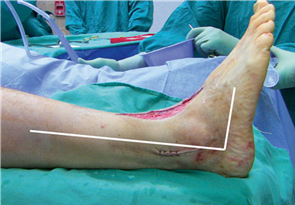

The patient is typically positioned supine on the operating table. A bump is placed under the ipsilateral hip to internally rotate the leg, bringing the foot into a neutral, upward-facing position, which greatly facilitates access to the medial column. A pneumatic tourniquet is placed either at the thigh or the calf, depending on surgeon preference and the planned proximal extent of the procedure. Intravenous prophylactic antibiotics are administered within one hour of incision, and a regional ankle block or popliteal sciatic nerve block is frequently utilized to provide preemptive analgesia and minimize volatile anesthetic requirements.

Clinical & Radiographic Imaging Archive